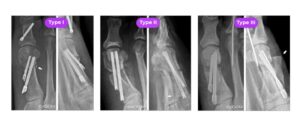

At the Comprehensive Foot and Ankle Institute, we perform minimal incision surgery for bunions, hammertoes, midfoot surgery, and rear foot surgery as well as ankle surgery. We do most of our procedures using the real minimal incision type procedures. This means we do not use large orthopedic screws or plates. It is now well-documented that the minimal incision surgery that many surgeons that are doing with large orthopedic screws result in blown out bunions. This will result in detrimental effects to patients. We specialize in the real minimal incision surgery for foot and ankle procedures. We use regenerative medical therapy to help with the bone healing as well. Below you will see an example of blown out bunion surgeries done by the large orthopedic screws.